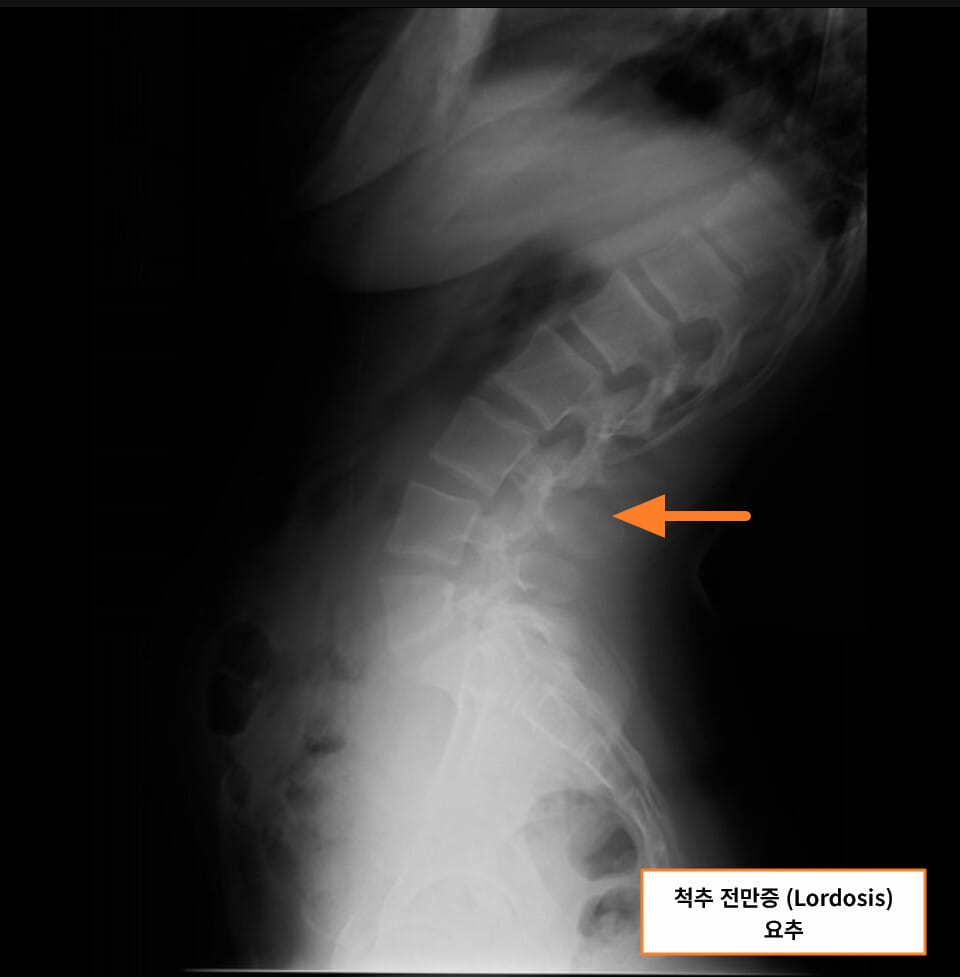

Lordosis (척추 전만증)

척추 전만증은 척추가 앞쪽으로 과도하게 휘는 상태로, 주로 허리(요추) 부위에서 관찰됩니다.

| 🟧 요추의 전만(curve)이 비정상적으로 증가 |

| 과도한 척추 전만은 복부가 돌출되어 보이게 하며, 신체 균형에 영향을 줍니다. |

| 🟧 요통 및 피로감 |

| 허리 근육이 지속적으로 긴장되며 통증이 발생할 수 있습니다. |